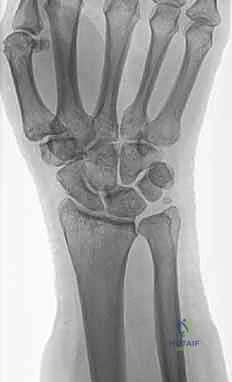

صورة طبية توضح كسر الناتئ الإبري

استخدام الأشعة السينية في التشخيص

1. الأشعة السينية (X-rays): بوضعيات متعددة (أمامية خلفية، وجانبية دقيقة). الوضعية الجانبية الحقيقية (True Lateral) حاسمة لاكتشاف أي خلع جزئي في المفصل (DRUJ).